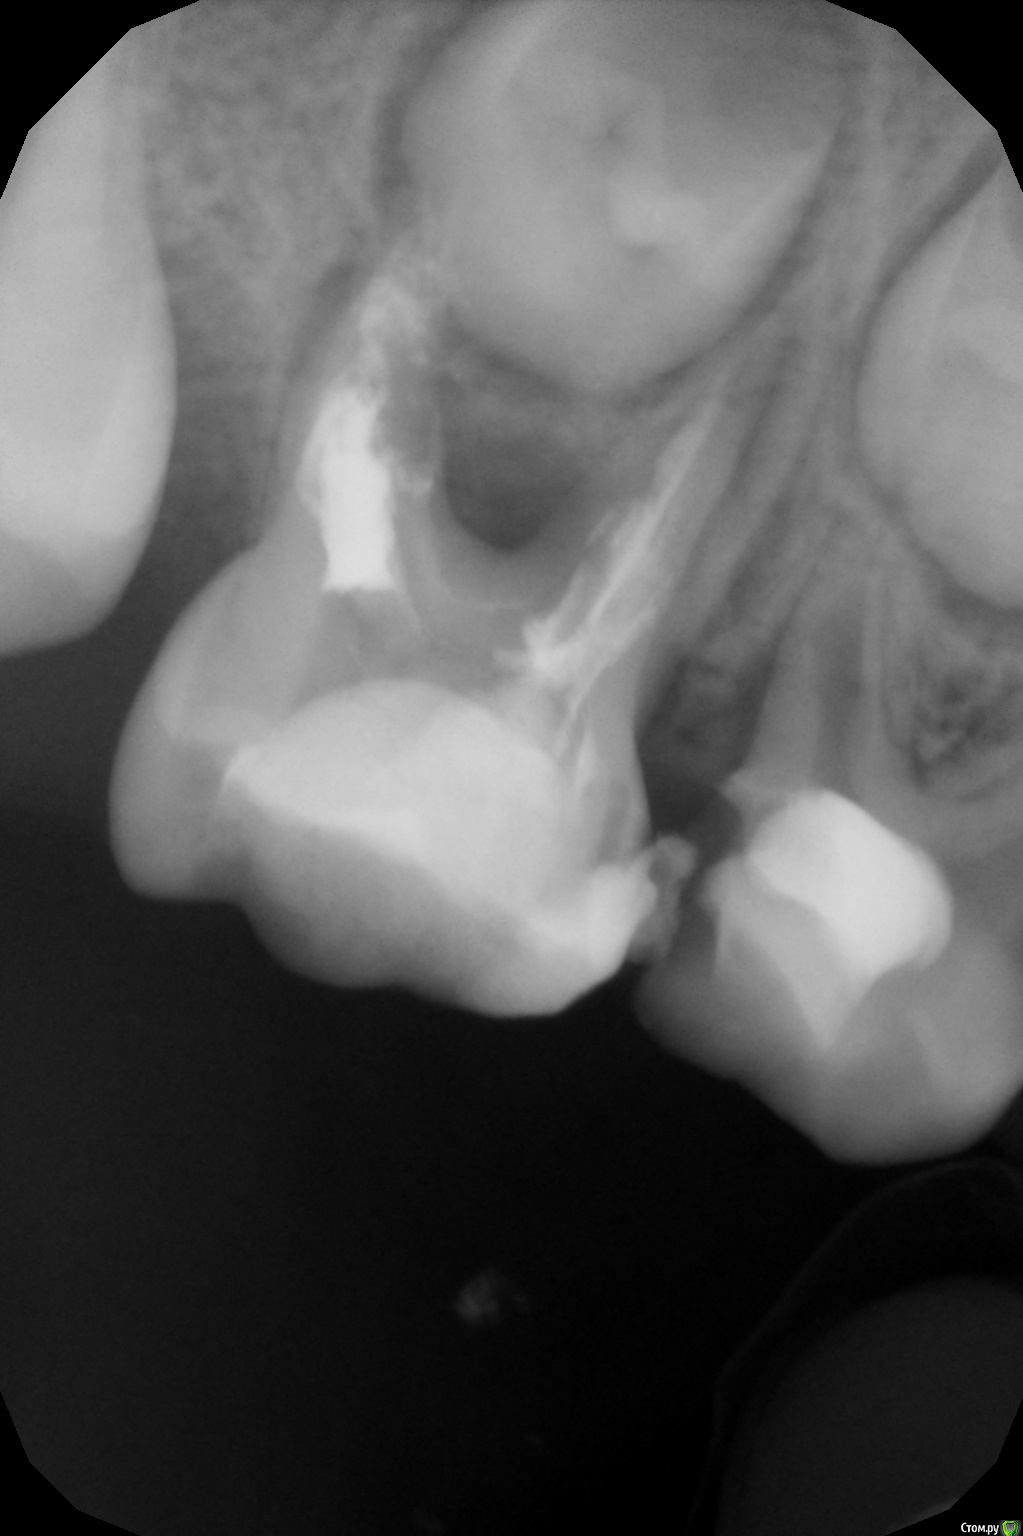

crown Опубликовано 13 июня, 2016 Поделиться Опубликовано 13 июня, 2016 5,5 лет, 8.5 - ранее лечен рф методом. Смущает дистальный корень, боюсь в процессе эндо будет перфо. Что думаете? Ссылка на комментарий

Джима Опубликовано 14 июня, 2016 Поделиться Опубликовано 14 июня, 2016 может, уже есть. машиной не лезьте, только руками, и родителям сразу говорите, что это "разведка боем", диагностическое препарирование, которое может закончиться удалением. временную с кальсептом, под ней видно будет, "пойдёт" зуб, или лучше удалить. 1 Ссылка на комментарий

crown Опубликовано 14 июня, 2016 Поделиться Опубликовано 14 июня, 2016 может, уже есть. машиной не лезьте, только руками, и родителям сразу говорите, что это "разведка боем", диагностическое препарирование, которое может закончиться удалением. временную с кальсептом, под ней видно будет, "пойдёт" зуб, или лучше удалить.Я так понял если будет кровить после кальсепта то удаление. Что то зачастили периодонтиты вот еще один. Что с этим делать? Ссылка на комментарий